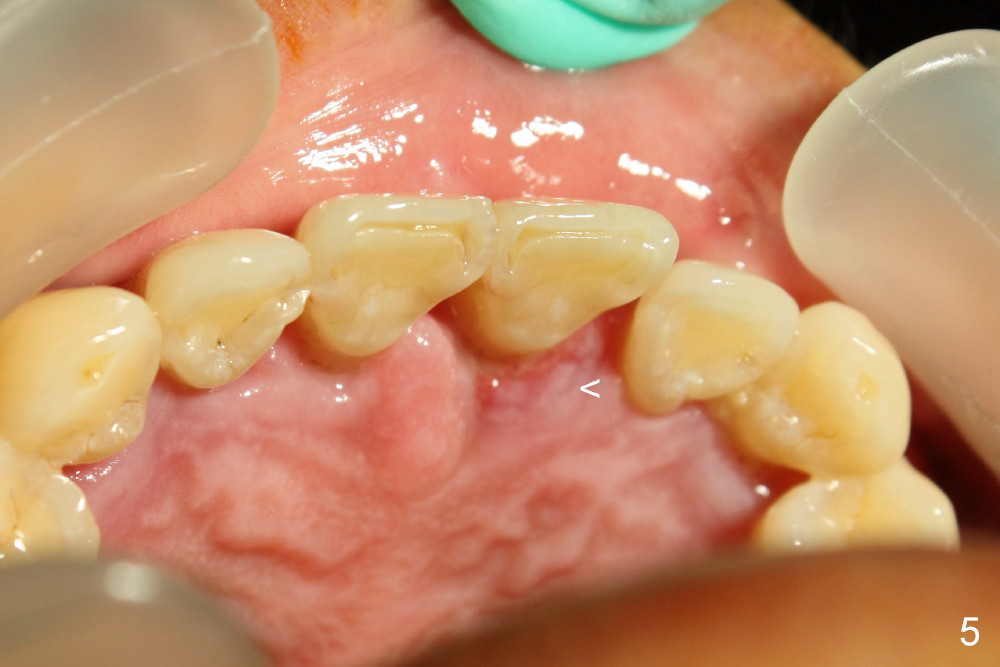

A 44-year-old man has advanced periodontitis (Fig.1,2). The infection resolves substantially 5 days post scaling & root planing (Fig.4,5). The two centrals have severe bone loss (Fig.3) and are going to be replaced by 5x20 mm implants (Fig.6).